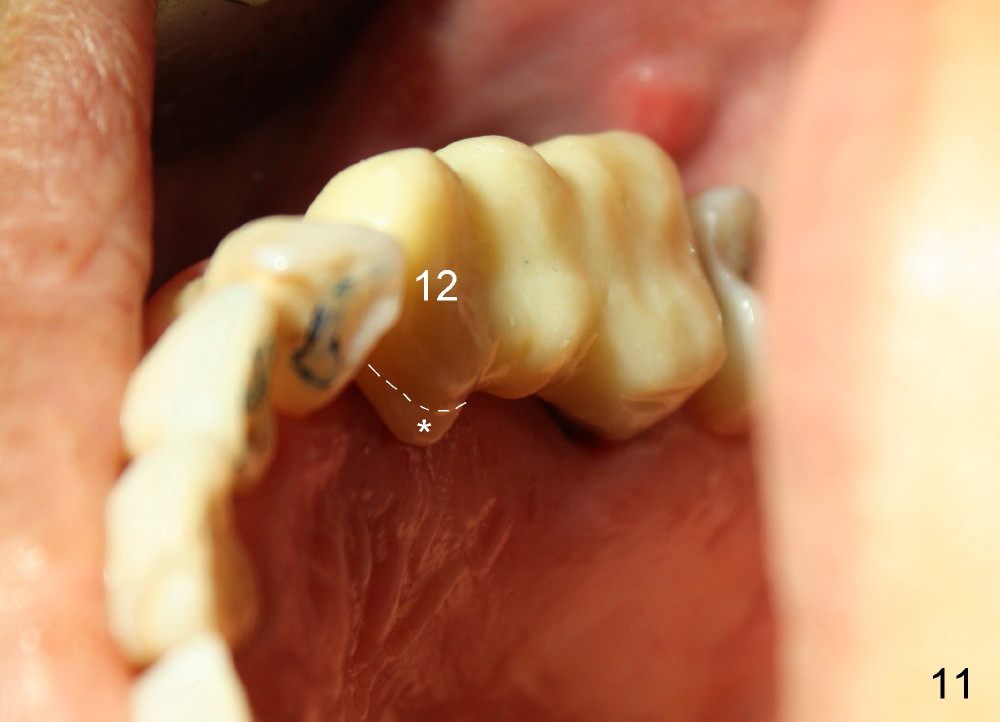

Buccal to #14 implant/abutment is a large defect, which is filled with allograft and Osteogen and covered by collagen membrane (Fig.9 M). The defect at the site of #12 is mesiopalatal, which is repaired in the same fashion (Fig.10: M). The collagen membrane is in turn protected by the "overhang" (extension) of the immediate provisional bridge (Fig.11,12 *). Once the wounds heal (Fig.13, 9 days postop), the extension is trimmed (Fig.14).